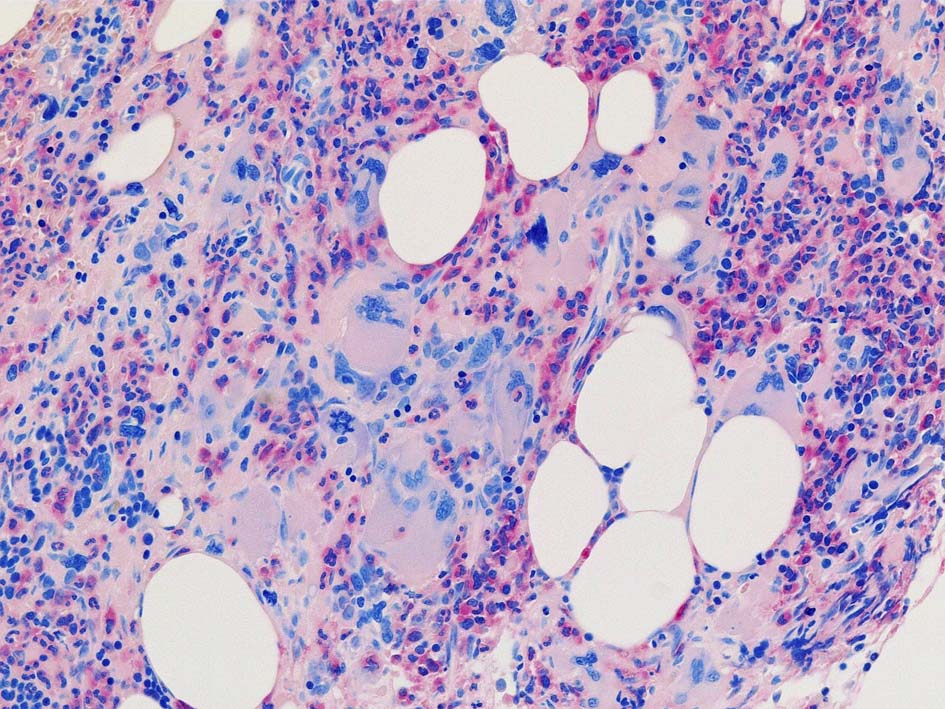

骨髄組織所見 bone marrow biopsy total 6mm in length

黒染する弾性線維の増生のほか, 赤く染まる膠原線維の増生が確認される. MF-2 fibrosis. 鍍銀染色の核染色をすると膠原線維の赤染がわからなくなるので行わない.